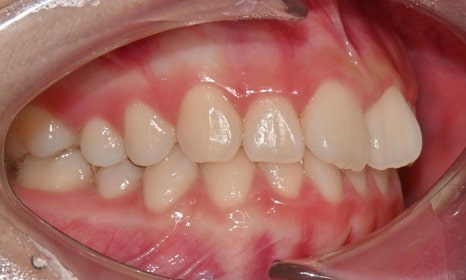

2025.3. 초진 (앞니 경미한 총생과 과개교합) - 연세정원치과

정밀진단 결과 위아래 앞니가 약간 겹쳐 있어 배열이 고르지 않은 상태였으며, 약간의 과개교합이 동반된 상태였습니다. 다만 골격적인 문제나 안모 불균형은 없었고, 측면에서도 돌출감 없이 비교적 안정적인 안모를 유지하고 있었습니다.

이러한 점을 종합적으로 고려해보았을 때 치아 배열의 개선과 교합 조정을 중심으로 한 비발치 교정 치료가 적합한 케이스였습니다. 또한 환자가 고등학생이라는 점, 그리고 학업과 일상 생활에 대한 부담을 최소화하고 싶다는 보호자의 의견을 반영하여, 인비절라인으로 선택하게 되었습니다.

이번 케이스는 인비절라인 Comprehensive로 치료를 진행하였으며, 치아 이동은 과도하지 않게 단계적으로 진행하기 위해 치간삭제를 최소한으로 적용하며 공간을 확보하는 방향으로, 총 33단계의 장치를 통해 치아 이동을 계획하였습니다.